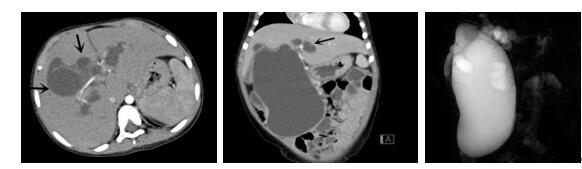

10、三维重建虚拟肝脏、胆道显像技术

三维虚拟肝脏技术是在二维影像学资料如CT等图像的基础上,通过三维重组软件和工具,比如青岛大学附属医院与海信医疗集团联合自主研发的海信计算机辅助手术系统(Hisense Computer Assisted Surgery,Hisense CAS),目前已投入临床并指导实际应用,利用该类系统对二维影像学的数据资料进行三维立体分析,重组形成立体的、有空间结构的、虚拟的肝脏三维图像。这项技术较传统的二维平面成像技术,有着明显的优势,3D虚拟肝脏技术可以构造出一个虚拟的、可视化的肝脏模型。通过对这种模型的观察,可以很容易地分辨出肝脏器官的组织结构、解剖特点,直观研究肝外胆总管的形态差异,明确肝内胆管的形态、走形、是否合并扩张、狭窄及结石,胰胆管合流的形态及共同通道内是否有狭窄、扩张和结石等病变情况,预先规划处理可能合并存在的肝内胆管扩张、狭窄或其他复杂胆道畸形,清晰地显示肝内脉管系统,包括门静脉、肝动脉及肝静脉的走行、分支,并可多角度、全方位观察病变胆道与其周围重要血管尤其是伴行的门静脉之间的解剖关系,大大提高了外科医师在术前对肝脏内部各管道结构及其变异判断的精确性和可靠性,精准地对病变进行判断和评估,还可根据患者自身的病变特点,制定出合理、个体化的手术方案,最大限度地降低术中和术后并发症发生率,并术中导航实时指导手术,提高手术的精准性和成功率。

图10:先天性胆管扩张症囊肿型三维重建虚拟肝脏、胆道显像

a 图为术前二维CT扫描图像,箭头所示为肝内胆管扩张;b 图为CT经多平面重组技术(MPR)图像后处理所得的重建图像,可显示胆总管明显扩张合并肝内胆管扩张;c 图为MRCP显示胆总管呈囊柱状扩张,直径>1 0 cm,伴肝内胆管扩张;d 图示Hisense CAS三维重建清晰显示肝脏、胆道系统及其与门静脉、肝动脉、肝静脉等之间的空间解剖关系;e 图示Hisense CAS可从任意角度以不同脏器组合显示,明确胆道系统与其伴行的门静脉系统的空间解剖关系;f 图示胆道系统立体形态及与肝脏整体的空间关系,箭头处显示肝内胆管狭窄部位发生于左右肝管汇入肝总管处。术前规划需行肝内胆管扩大成形术。

图11:先天性胆管扩张症梭状型三维重建虚拟肝脏、胆道显像

a 图为术前二维CT扫描图像,箭头指示肝内胆管扩张;b 图为CT经多平面重组技术(MPR)所得的重建图像,可粗略地判断病变胆管的位置;c 图示术前Hisense CAS三维重建清晰显示胆管的病理形态及其与肝内三套血管系统的解剖关系;d 图示胆道系统与其伴行的门静脉系统的空间解剖关系;e 图为胆道系统立体形态,箭头处指示迷走胆管,源自肝脏直接汇入胆总管。术前规划先将迷走胆管与肝总管吻合成形,再行肝总管空肠Roux-en-Y吻合术。

图12:先天性胆管扩张症梭状型合并左右肝管分别汇入胆总管囊肿三维重建虚拟肝脏、胆道显像

a 图为术前二维CT图像;b 图为CT经多平面重组技术(MPR)所得的三维重建图像,可粗略地判断病变胆管的位置;c 图为MRCP显示胆总管梭状扩张;d 图为术前Hisense CAS三维重建显示胆管的分布走形及其与肝内三套血管系统的解剖关系;e 图为胆道系统立体形态及与肝脏整体的空间关系,箭头处显示对于左右肝管分别汇入胆总管囊肿中,整个肝总管也明显扩张而成为囊肿的一部分。术前规划为先将囊肿完全切除,左右肝管合并成形后再与空肠吻合。